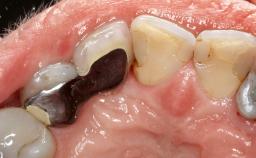

This case describes both a surgical and an anti-infective approach for the management of peri-implantitis, including treatment of the entire dentition to eliminate any deep periodontal pockets that could serve as reservoirs for bacterial re-colonization at the implant site. A 65-year-old female patient was referred to the periodontist in 2013 for assessment and management of an infection at implant 12. On examination, probing depths at implant 12 were 11 mm with suppuration and bleeding on probing.